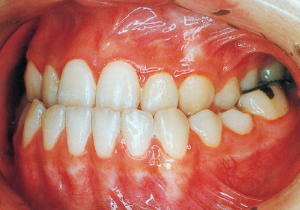

Age at Initial Visit: 8 years 1 month, Female / Protruding lower bite. Protruding lower jaw

1 Initial Visit 8-29-’79

Although there were many missing deciduous teeth, the number of permanent teeth was not problematic (4). The amount of negative overjet was significant (1). On cephalometric radiographs, the mandibular ramus was not relatively long, but the large gonial angle and the long mandibular body were noticeable, indicating an overall tendency of the mandible to project inferiorly and anteriorly. High lower facial height was also characteristic.

A potential predisposition to mandibular protrusion was clearly evident.